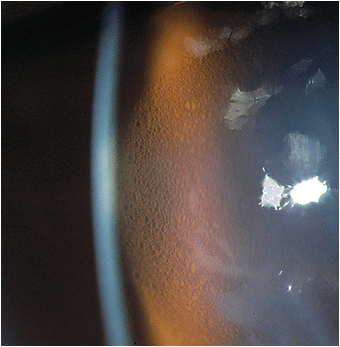

Corneal edema occurs when there is an imbalance of hydration in the cornea.

Corneal epithelium offers twice the resistance to water flow compared to the endothelium. This anterior portion of the cornea is composed of 4-6 layers of cells. The layers are composed of squamous, basal, and wing cells. Swelling seen in the epithelium is predominantly extracellular, with fluid beginning to accumulate in the space between the basal epithelial cells and the bridging desmosomes. The anteriormost wing cells are usually not affected, as there is resistance to this anterior fluid movement situated in this layer. Epithelial edema can range in clinical presentation from microcystic edema to large bullae, characteristic of bullous keratophy. In addition, epithelial edema is the most common form of edema found in patients with acute ocular hypertension.